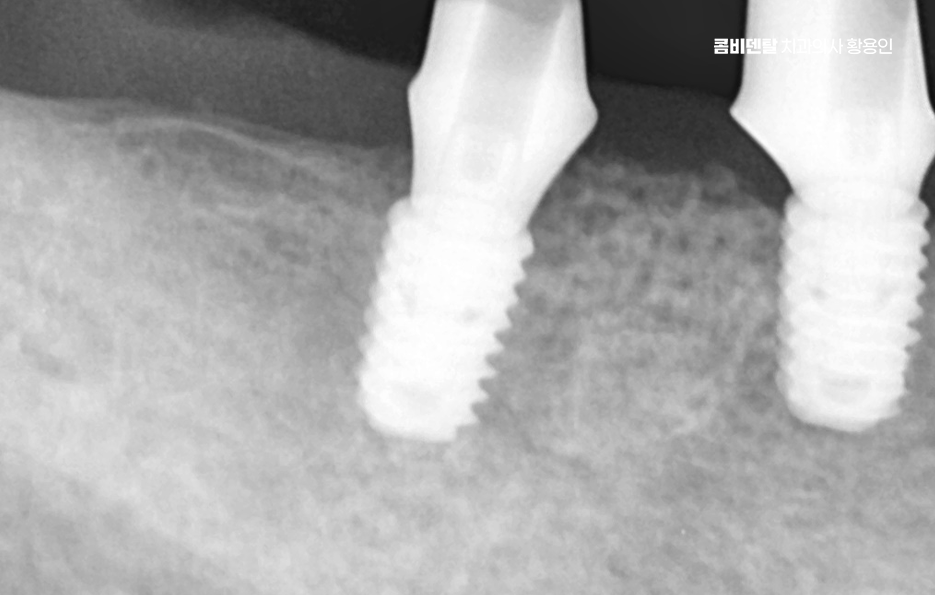

일반적으로 발치 후 뼈 상태가 양호하다면, 약 2~3 개월 정도의 치유 기간을 거친 다음 임플란트를 심게 되는데 요즘은 상황에 따라 바로 임플란트를 식립하는 ‘즉시 식립’ 방식도 많이 사용되고 있으며 단, 이러한 치료 방식은 뼈의 상태가 충분히 튼튼하고 염증이 없는 경우에 가능하며 경험 많은 치과의사와 함께하는 것도 중요할 수 있었어요

치아 발치 후 임플란트 치료 과정은 처음에 CT나 파노라마 엑스레이를 통해 뼈의 양과 밀도, 신경 위치를 정확히 확인하는 것부터 시작되며 치아가 빠진 자리에 뼈가 많이 흡수되어 있다면, 임플란트를 심기 전에 뼈이식을 먼저 해야 할 수 있지만 반대로 뼈 상태가 좋다면 임플란트를 심고, 보통 3개월 동안 뼈와 잘 붙을 때까지 골융합 과정을 기다리게 되며 골융합이 잘 이루어진 뒤에는 그 위에 지대주라는 연결 부품을 끼우고, 그 위에 최종 보철물을 씌우면서 치료가 마무리되고 있어요